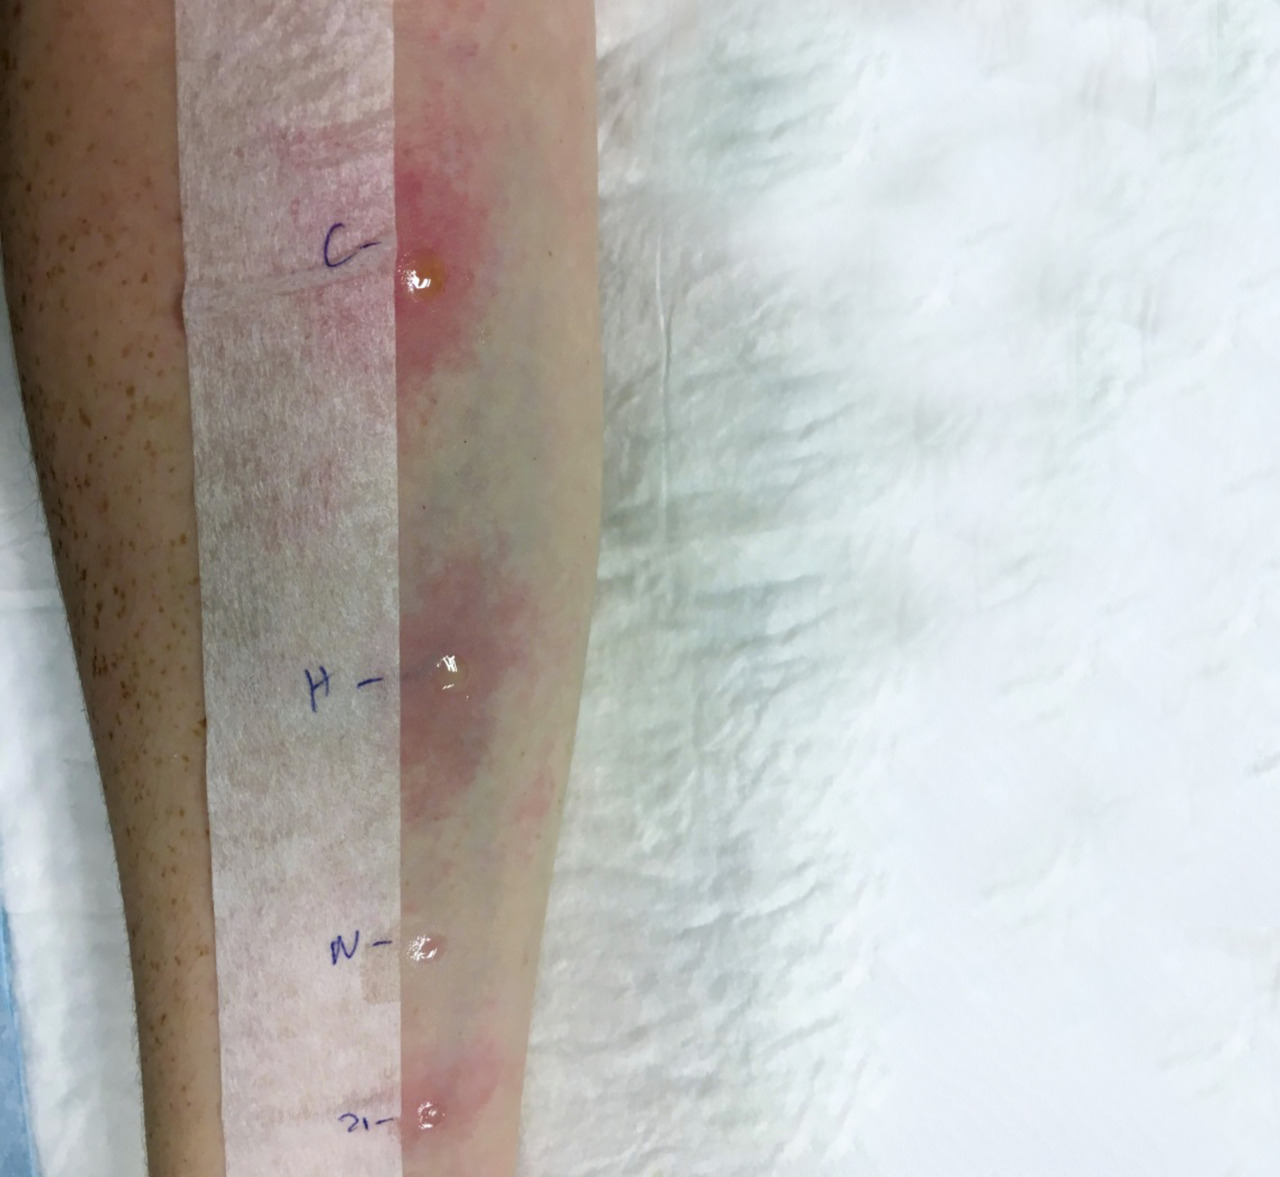

Un patient ayant présenté une anaphylaxie devra être orienté dans un délai de 4 à 6 semaines vers un allergologue afin d’identifier l’allergène responsable, voire de prescrire les différentes médications en cas d’urgence si cela n’a pas été fait lors du passage aux urgences. Les tests reposent en première intention sur les tests cutanés (prick-tests, habituellement poursuivis par des intradermoréactions pour les venins et les allergies médicamenteuses) [fig. 2 et 3]. Cela permettra ensuite d’en assurer l’éviction ou de proposer en particulier une immunothérapie en cas d’allergie aux hyménoptères. Il sera remis ensuite une carte d’allergique au patient. Un plan d’action spécifique visant à éviter la récidive sera rédigé, comme un projet d’accueil individualisé (PAI) pour les enfants et adolescent d’âge scolaire. La prescription d’un système auto-injectable d’adrénaline repose sur les données du consensus européen, qui retient 6 indications absolues : anté­cédent d’anaphylaxie alimentaire ou au latex, antécédent d’allergie alimentaire induite par l’effort, antécédent d’anaphylaxie idiopathique, coexistence d’un asthme et d’une allergie alimentaire systémique, allergie aux hyménoptères, patho­logie mastocytaire.